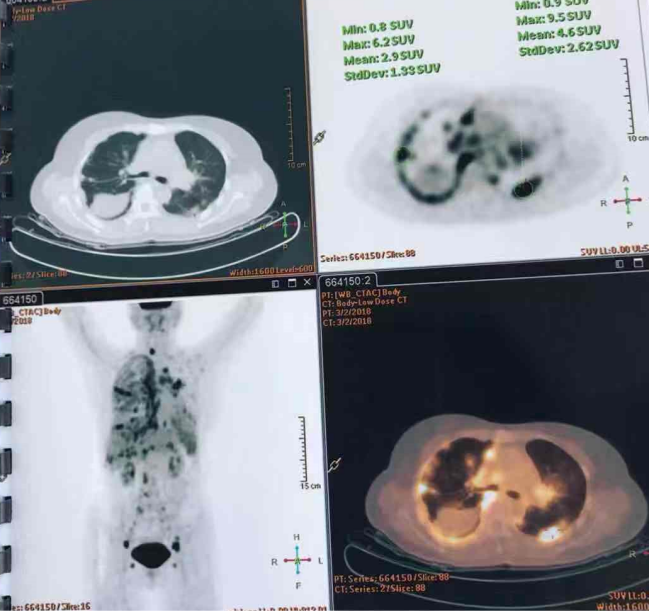

医学慕课 肺部结节8年 上海瑞金医院病例